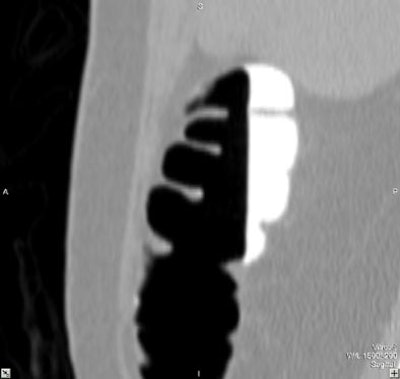

| Virtual colonoscopy images of an asymptomatic 56-year old woman who ingested small aliquots of nonionic iodinated contrast, without dietary restrictions, prior to virtual colonoscopy. The evening before the exam, the patient ingested a half dose of mild cathartic, markedly reduced from standard regimens. Images top to bottom: Sagittal view of cleansed colon following the preparation; corresponding cutaway view; volume-rendered endoluminal views of the same region demonstrate opacificed material in the colon. Further below, the same set of images after the subtraction software has removed opacifying material and reconstructed a natural appearing colonic mucosa, as seen in sagittal; cut-away; and endoluminal (fly-through) views. The green arrow points to some of the contrast which is layering in the dependent portion of the colon. All images courtesy of Dr. Michael Zalis. |